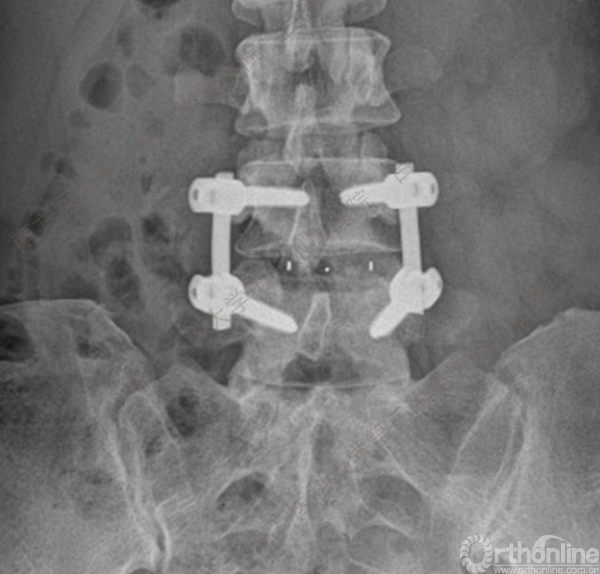

随着社会老龄化进程加快,胸腰椎退行性病变的治疗已经成为脊柱学术界的一个热点话题。MIS-TLIF手术可以治疗多种不同的胸腰椎退行性疾病,南方医科大学第三附属医院吕海教授结合病例为我们一一展示了该术式在治疗不同胸腰椎疾病时的具体手术过程。